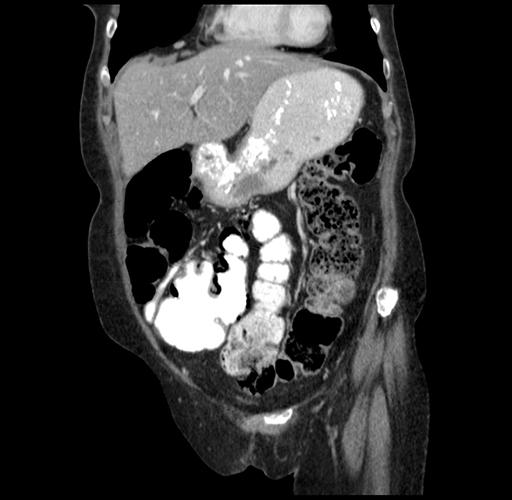

Pre-Chemo: Axial Venous

Pre-Chemo: Coronal Venous